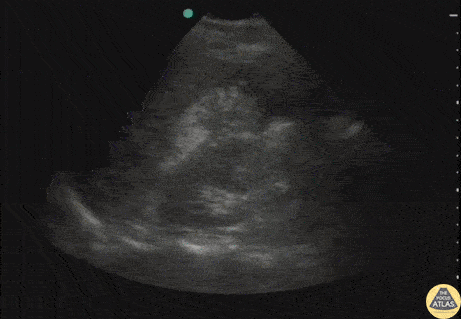

Biliary - Ruptured Viscus from Trauma

Pt stuck by car while riding bike. Perihepatic view on FAST exam revealed a perforated viscus (gastric rupture). Note the free air within the fluid. Image courtesy of Robert Jones DO, FACEP @RJonesSonoEM Director, Emergency Ultrasound; MetroHealth Medical Center; Professor, Case Western Reserve Medical School, Cleveland, OH View his original post here